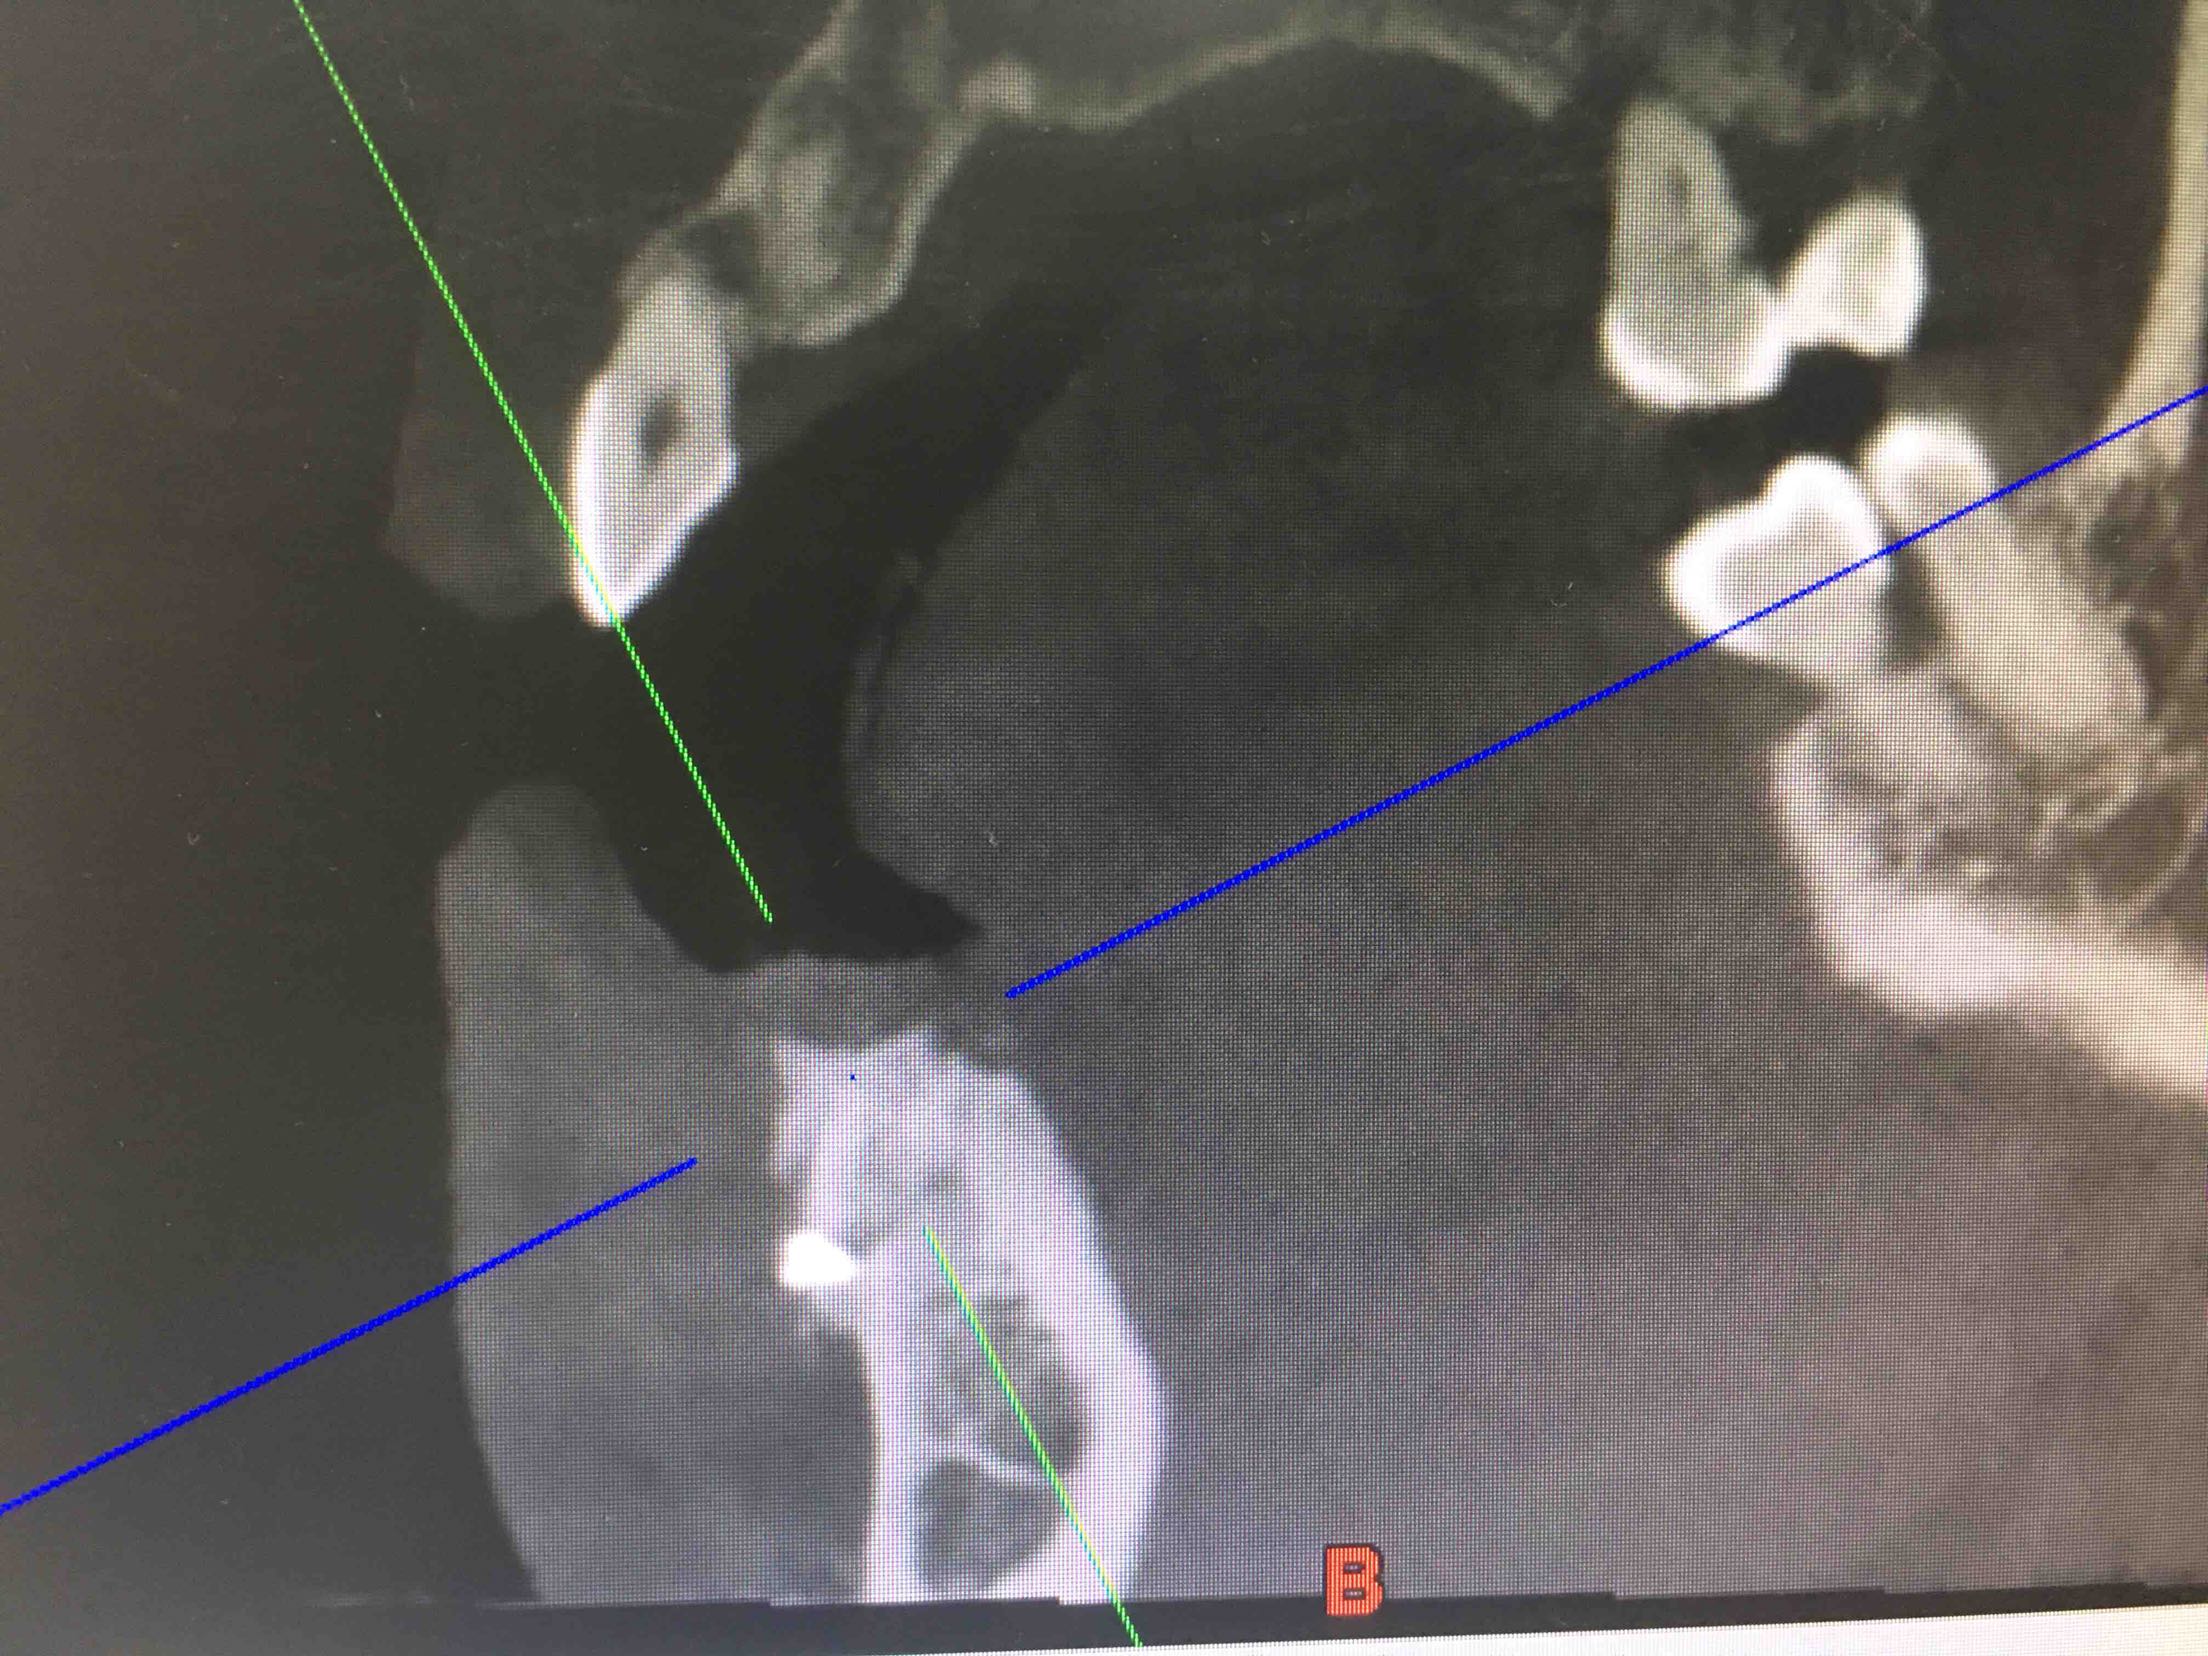

41、43、44牙松动2-3度,42牙缺失,全景片及CBCT显示牙槽骨吸收严重。

两周后,局麻下,翻瓣拔除44牙,在41、42根方环形钻取骨块,钛钉固定于43牙骨缺损处,Bio-ss骨粉0.25g,海奥生物膜,严密缝合!嘱半年后植牙!